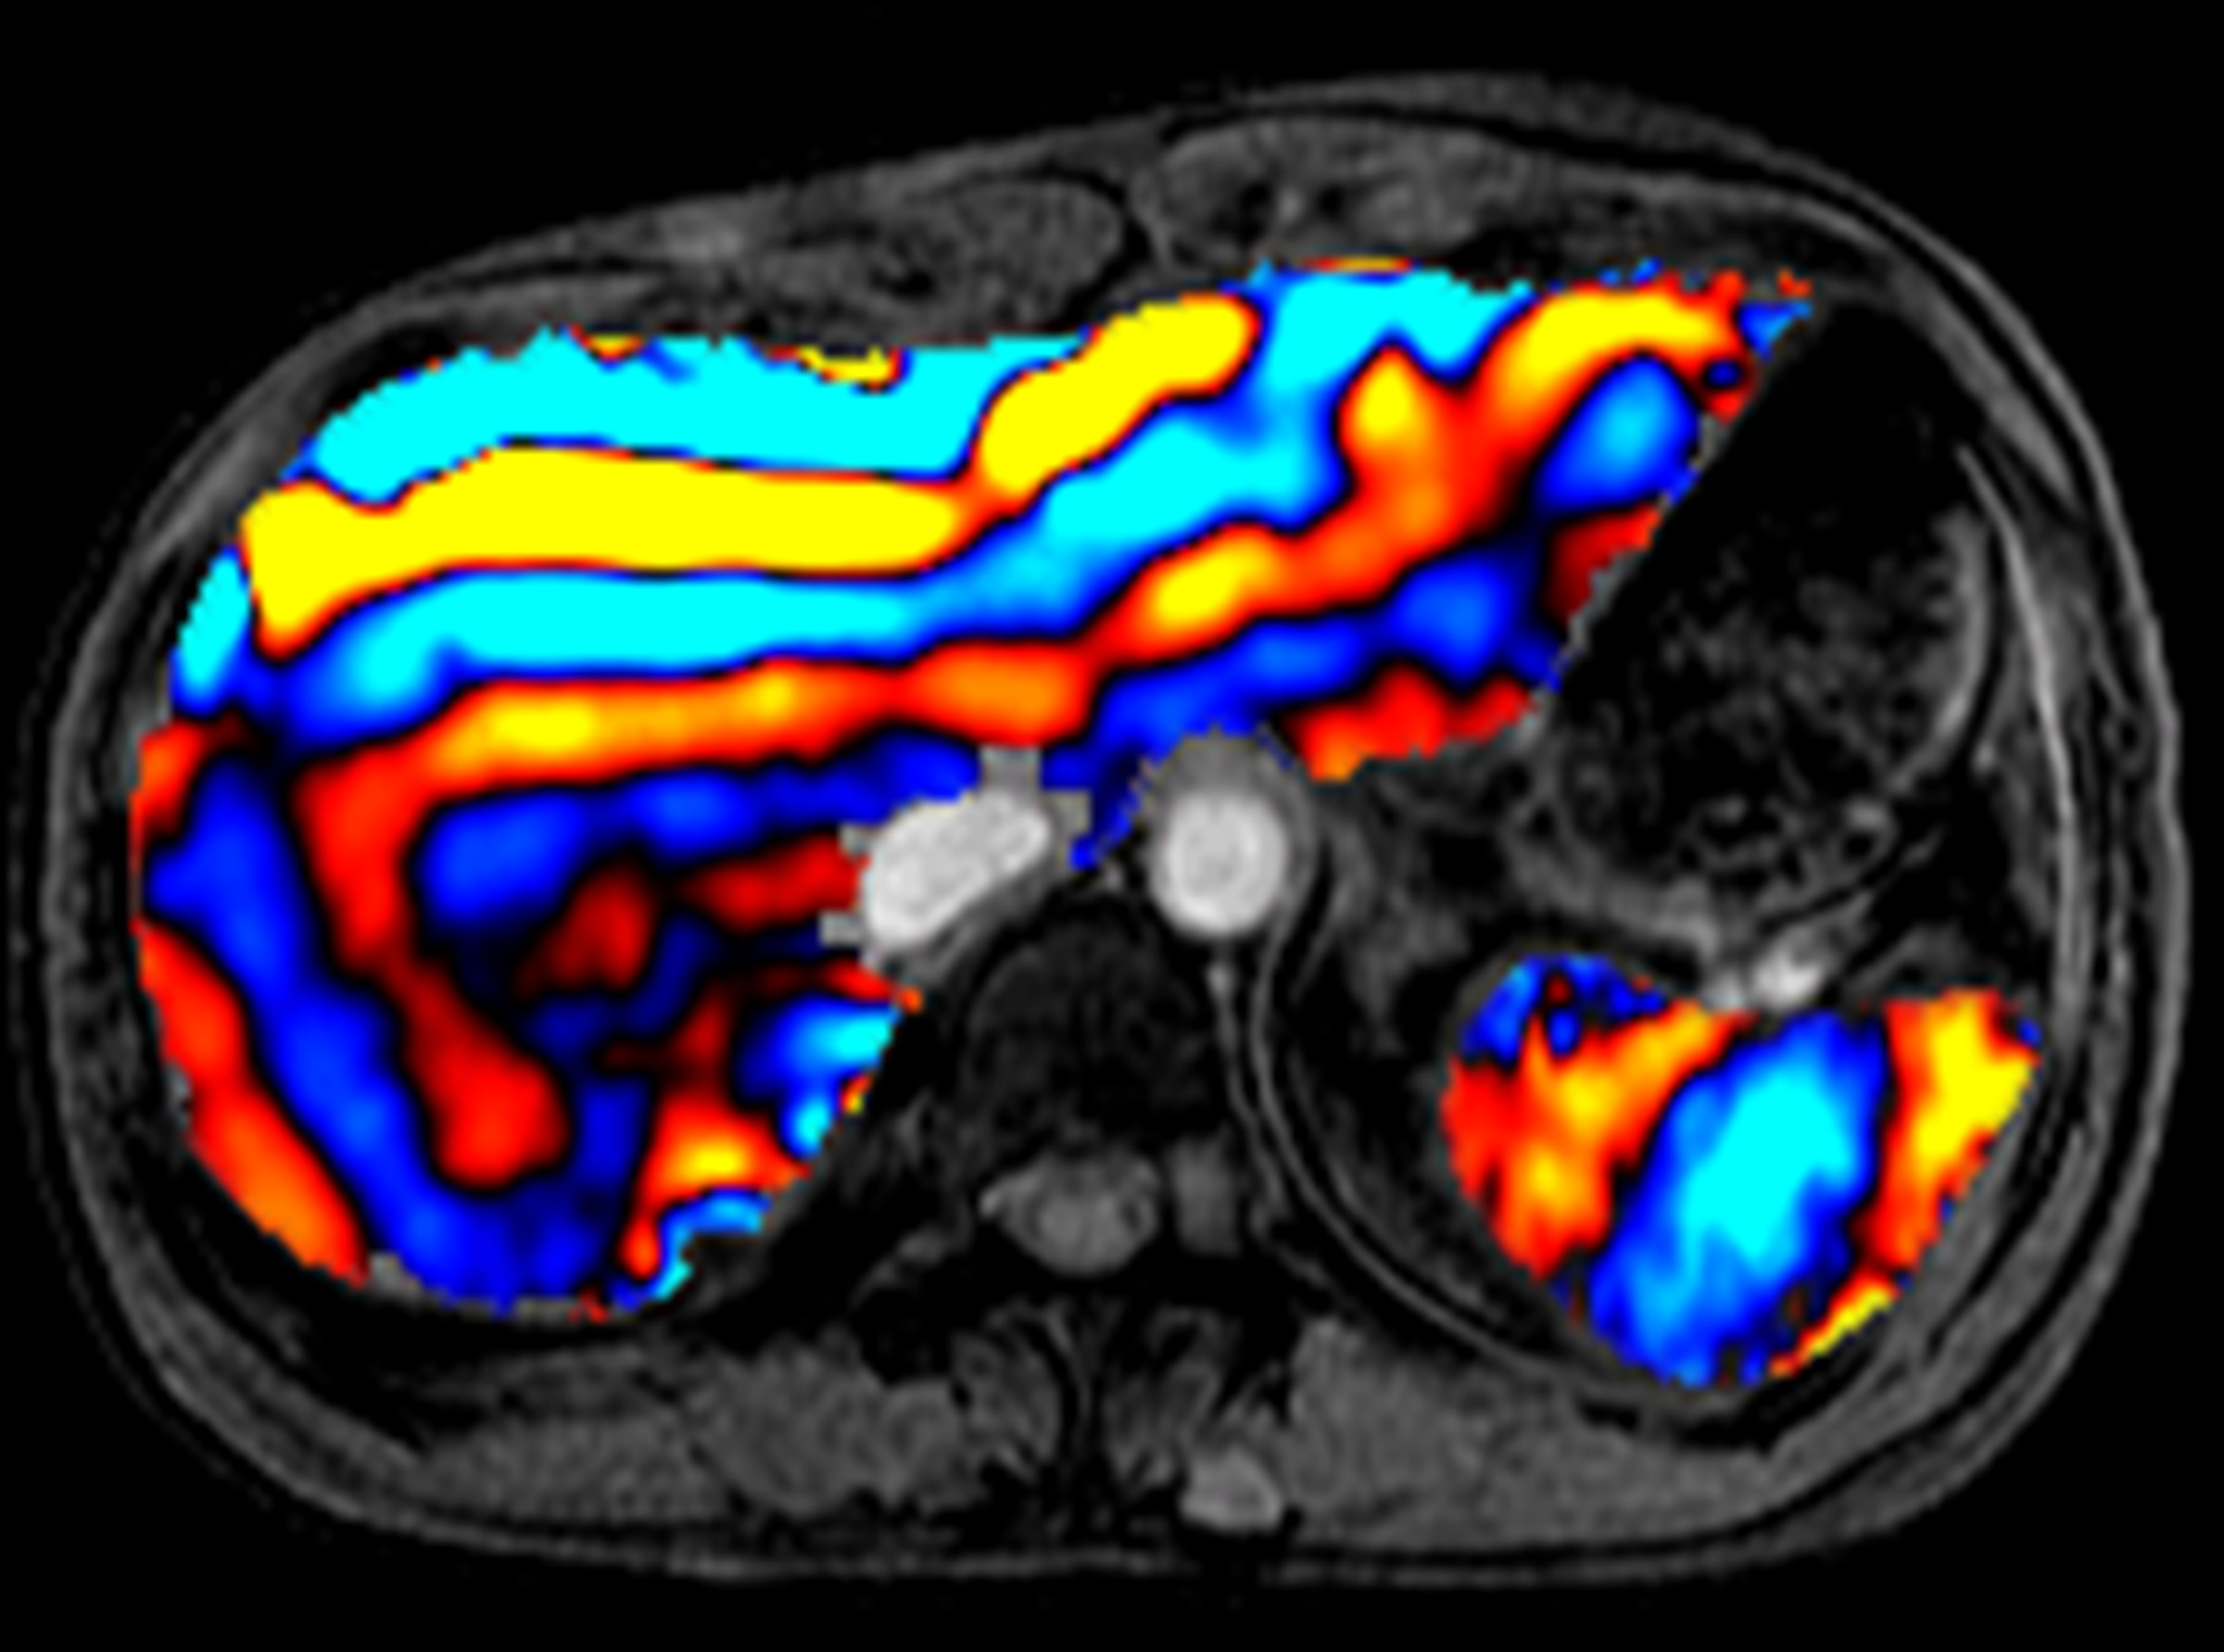

From pubs.rsna.org

Liver MR Elastography Technique and Image Interpretation Pearls and What Is Liver Elastography Liver elastography is used to check for liver fibrosis (scarring). A liver elastography is a noninvasive procedure that doctors use to determine the health of a person’s liver. Liver elastography is a noninvasive test that measures the stiffness of your liver tissue. This can be caused by a recent liver illness. It can help diagnose liver disease, such. An elastography. What Is Liver Elastography.